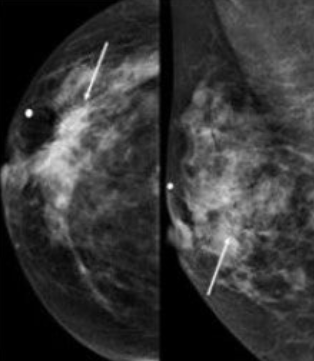

- 40대~: 매년 유방촬영술(mammography)